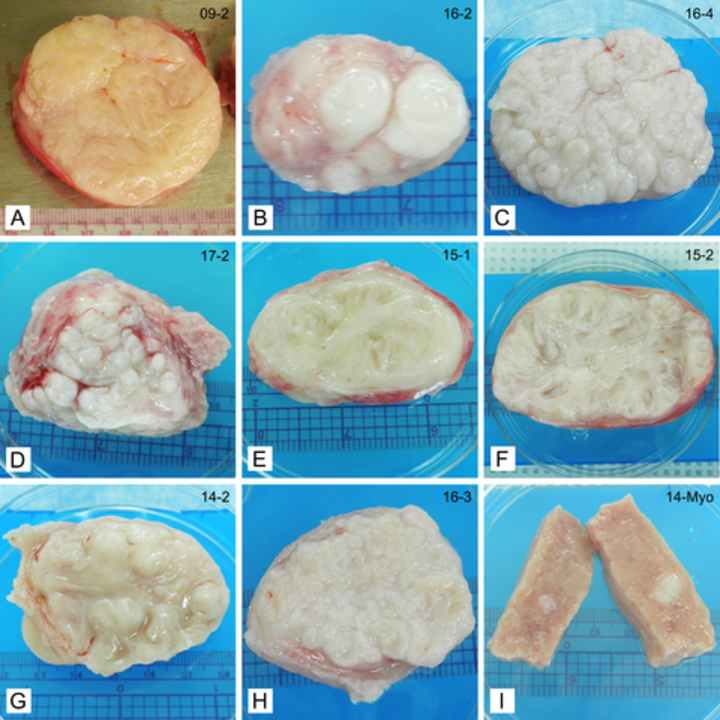

Recognizing Heterogeneity in Fibroids Could Expand Treatment Options …

MR imaging of atypical fibroids